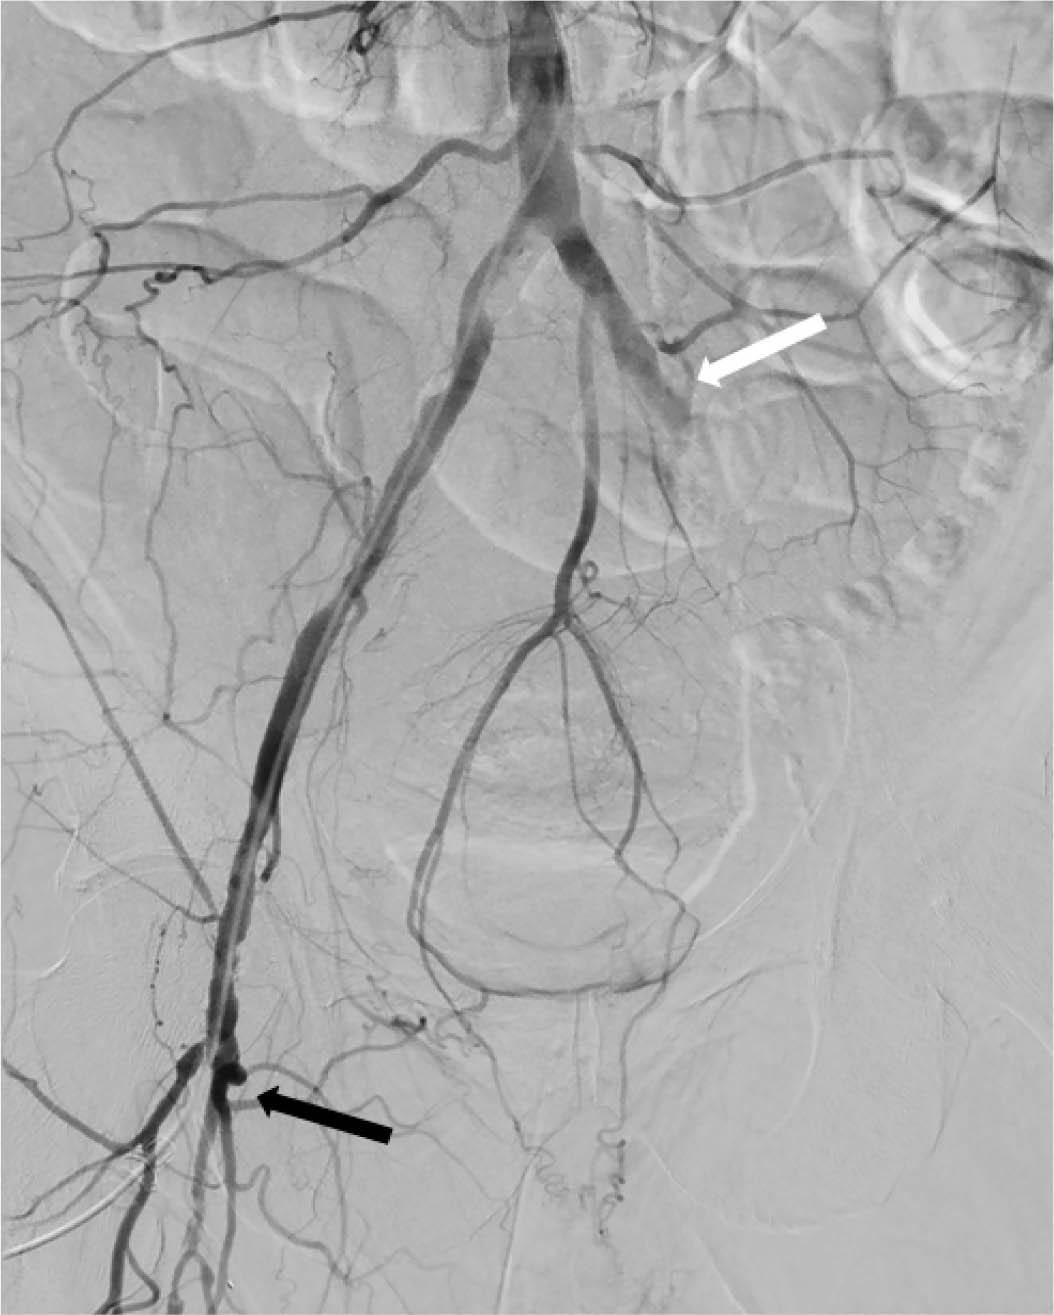

Figure 2